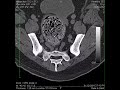

páteř / syndrom cauda equina

Foraminální cauda equina.

cauda equina syndrom